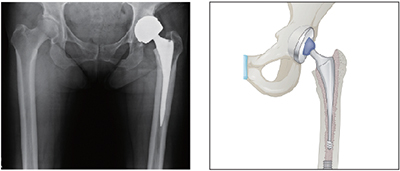

고관절인공관절치환술

• 대표적으로 대퇴골두무혈성괴사, 대퇴경부골절, 고관절퇴행성관절염과 같은 질환으로 인해 많이 시행합니다.